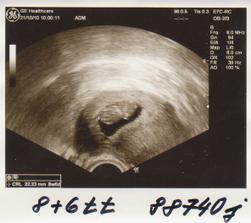

Taááákže 2. KET při 3. IVF